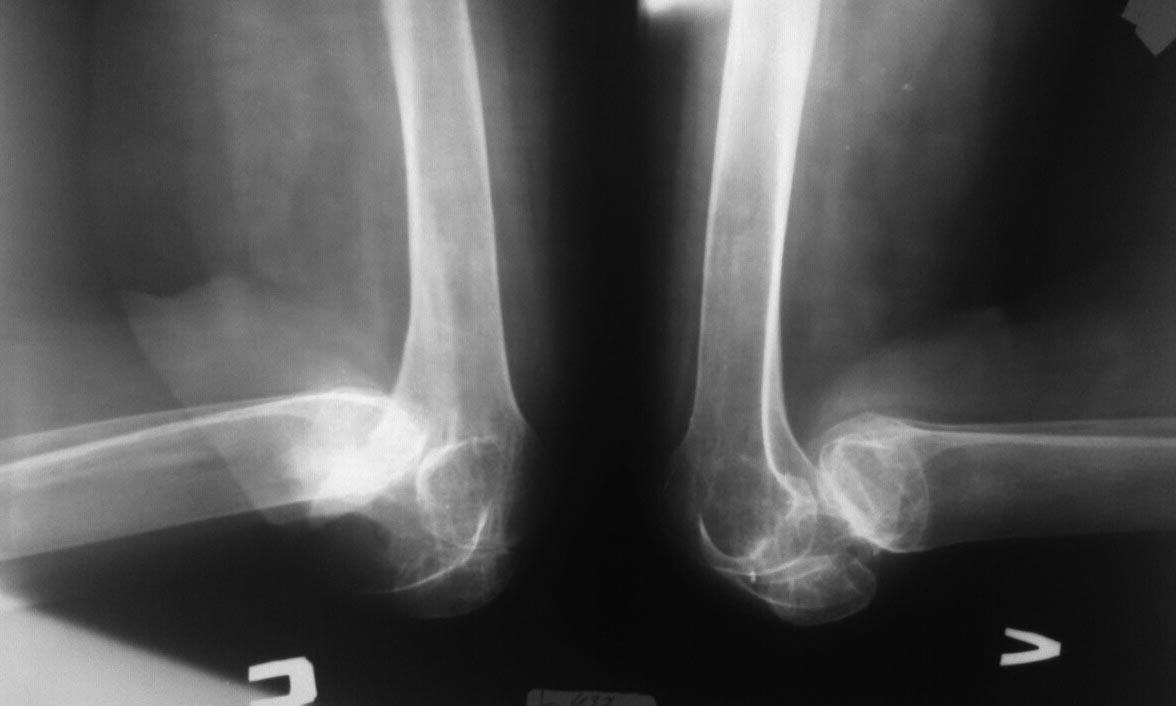

Девочка 16 лет, 4 года назад по поводу ожога пламенем тяжелой степени

обеих нижних конечностей она лечилась в сельской больнице, несколько

этапов аутодермопластики, и в настоящее время обратилась в отделение

травматологии и ортопедии за помощью.

Если честно, такую категорию больных никто давно не помнит, 4 года как

она не ходит, материальная сторона больной, естественно, не может

позволить ей куда то выехать и лечиться. Наш диагноз: Двухсторонняя

постожоговая контрактура коленных суставов, вывих голеней кзади.

Фото и рентген снимки прилагаются. Мы думали о метаплазии по Вредену,

Капсулотомии по Вильсону, Резекции суставных поверхностей и артродезе,

можно в аппарате Илизарова, но во всех случаях сомнения и вопросы:

Сможем ли одномоментно вывести конечность в более правильное положение,

не рановато ли с артродезирванием в 16 лет? Буду рад и признателен

советам форума